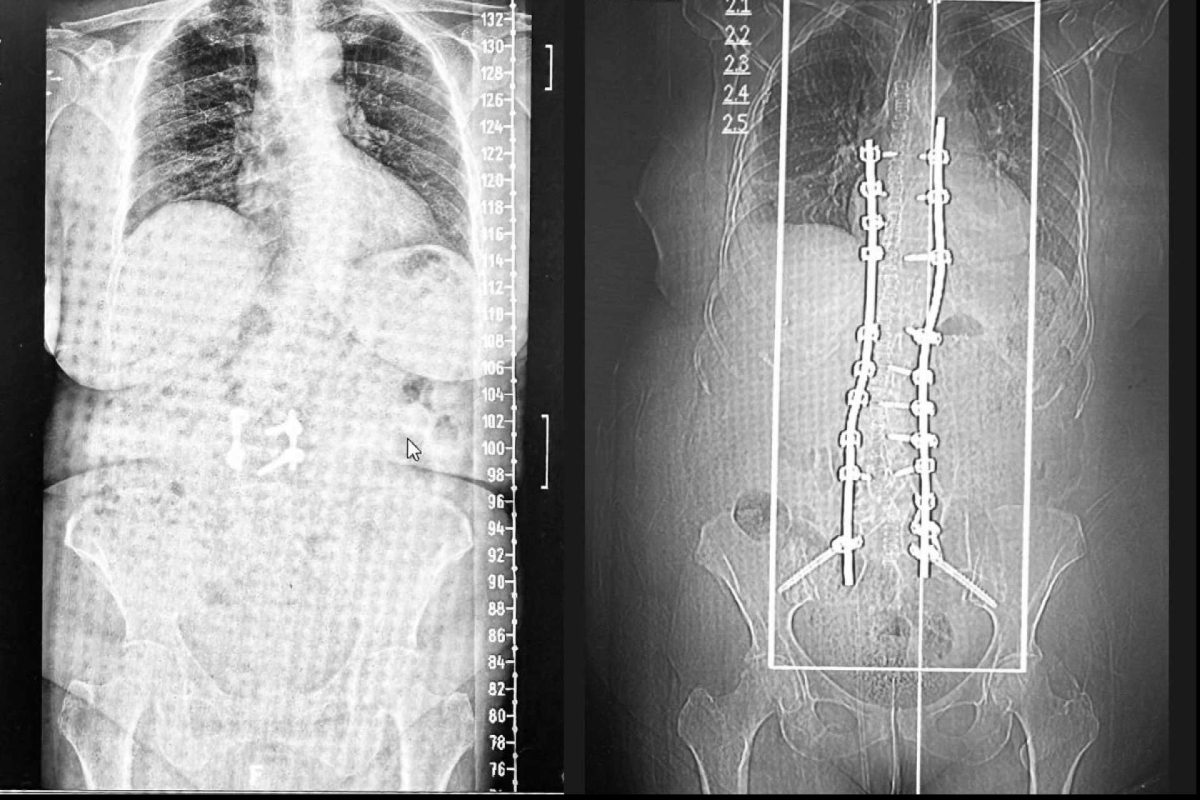

La revolución 3D en la cirugía de escoliosis en el adulto; entrevista con el Dr. Carlos Botella-Asunción

La escoliosis degenerativa del adulto es una afección que afecta a un número creciente de personas mayores, provocando dolor crónico y limitaciones funcionales. Gracias a los avances tecnológicos, el tratamiento quirúrgico de esta condición ha experimentado una transformación significativa. El Dr. Carlos Botella-Asunción, neurocirujano con más de 35 años de experiencia, nos explica cómo la […]